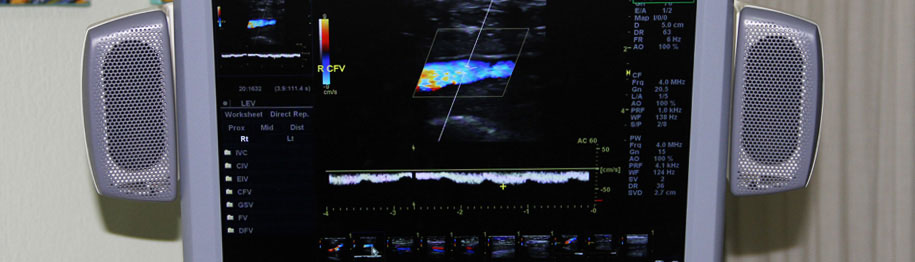

Tο ιατρείο μας παρέχει πλέον τη δυνατότητα εκτέλεσης κατ’ Οίκον όλων των εξετάσεων υπερηχογραφημάτων και triplex αγγείων. Με την καινούρια, φορητή και υπερσύγχρονη μονάδα υπερήχων NextGen LOGIQ e, General Electric (τελευταίας γενιάς) παρέχουμε την δυνατότητα για άμεσες λύσεις σε διαγνωστικά προβλήματα ακόμα και σε ασθενείς που δεν έχουν δυνατότητα μετακίνησης. Έτσι ο ασθενής και η οικογένειά του αποφεύγουν την ταλαιπωρία διακομιδής του σε νοσοκομεία ή διαγνωστικά κέντρα. Οι φορητοί υπερηχογράφοι μπορούν πλέον να εκτελέσουν όλες τις εξετάσεις, με τη βασική προϋπόθεση να είναι σύγχρονης κατασκευής. Η απουσία ακτινοβολίας και ο εύχρηστος τρόπος χρήσης καθιστούν την εξέταση πολύ προσιτή.